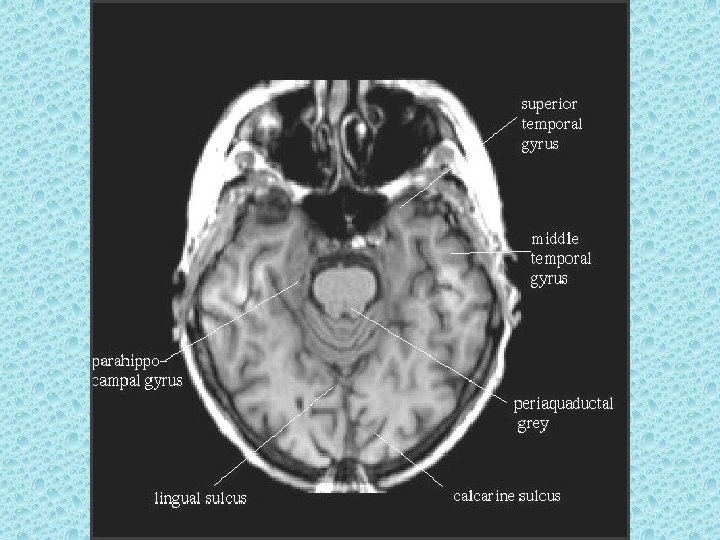

SEREBRAL LOBLAR • • Frontal Paryetal Oksipital Temporal

SEREBRAL PARANKİMDE BULUNAN YAPILAR • • Beyaz ve gri cevher Girus ve sulkuslar Lentiform nükleus: Putamen ve globus pallidus İnternal ve eksternal kapsül Talamus Kaudat nükleus ve korpus kallozum Ventriküller Koroid pleksus

POSTERİOR FOSSADA BULUNAN YAPILAR • • • Serebellum Beyin sapı 4. ventrikül Vermis Transvers ve sigmoid sinüs